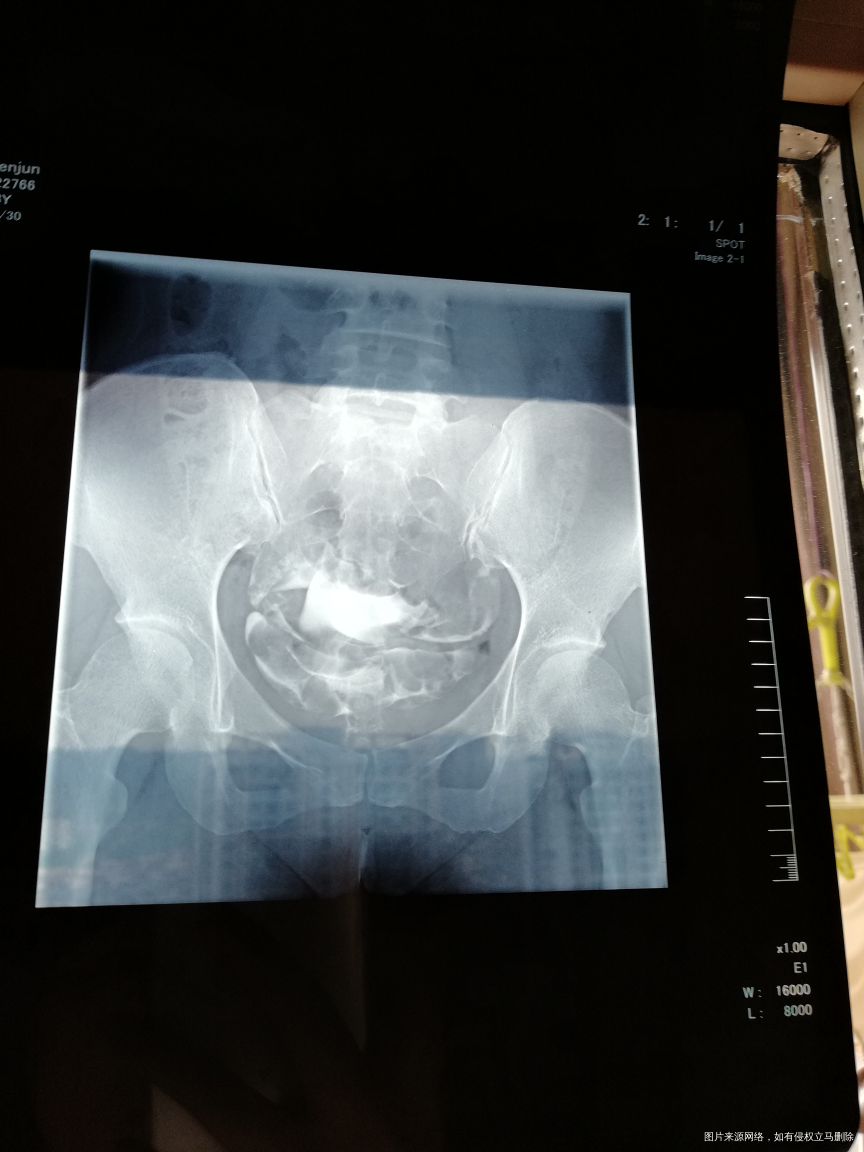

麻烦帮我看看输卵管碘水造影检查结果。我这样怎么治疗,是不是需要做试探婴儿

您好,输卵管通畅的就可以怀孕试试,如果确实怀孕困难可以选择腹腔镜手术,或者试管婴儿。

双侧输卵管通的!上举,可以试孕三个月看看。